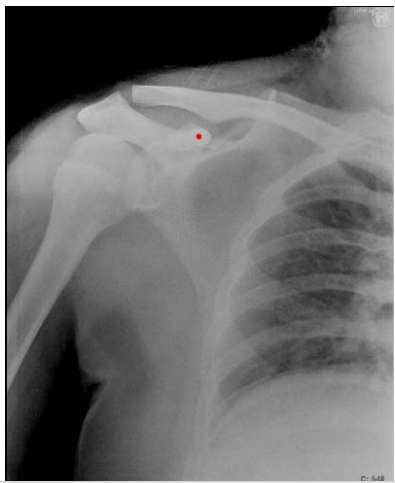

9. 下列何者不附著於附圖X光照片中,紅點所標示的部位?

(A)胸小肌 (B)喙肱肌 (C)肱二頭肌短頭 (D) 大圓肌